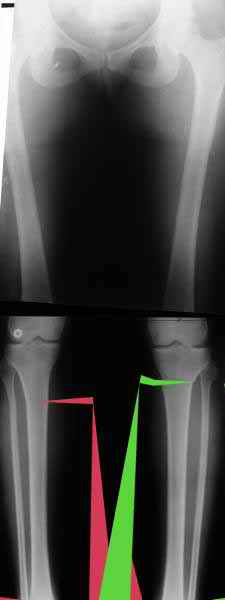

Из приведнной схемы не совсеим понял что означают разноцветные линии.

И зачем латерализация периферического фрагмента. Я всегда делаю медиализацию. См схему. И для данного случая медиализация подходит как нельзя лучше.

Черные - это нынешняя механическая ось. Красные - это планируемая правильная ось.

a> Я всегда делаю медиализацию. См схему. И для данного случая

Медиализация - это чисто эстетический прием, как я понимаю. Поскольку если делать остеотомию ниже вершины деформации, для восстановления оси надо делать смещение по ширине, в данном случае как раз латерализацию.

А вот на схемке без осей - там на разных уровнях (который правильнее?) устранение варуса чисто открытым клином без медиализации-латерализации. Если как-то так сделать - этого недостаточно будет?